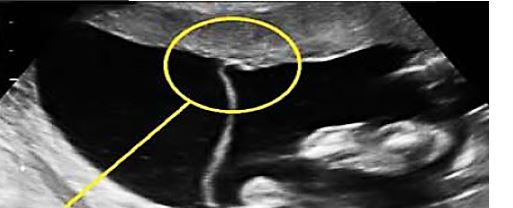

What is this?

Multiple Gestation

• US of intertwin membrane showing “T Sign” = Monochorionic twins

• Identical Twins (Monozygotic)

• Diamniotic (2 amniotic sacs)